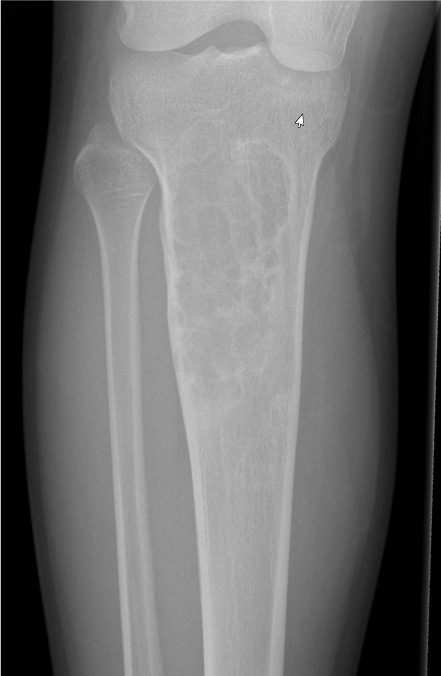

X-ray

Most common anterior cortex of tibia

Soap-bubble appearance

Eccentrically located

- well circumscribed

- slightly expansile

- cortical thickening

- little or no periosteal reaction